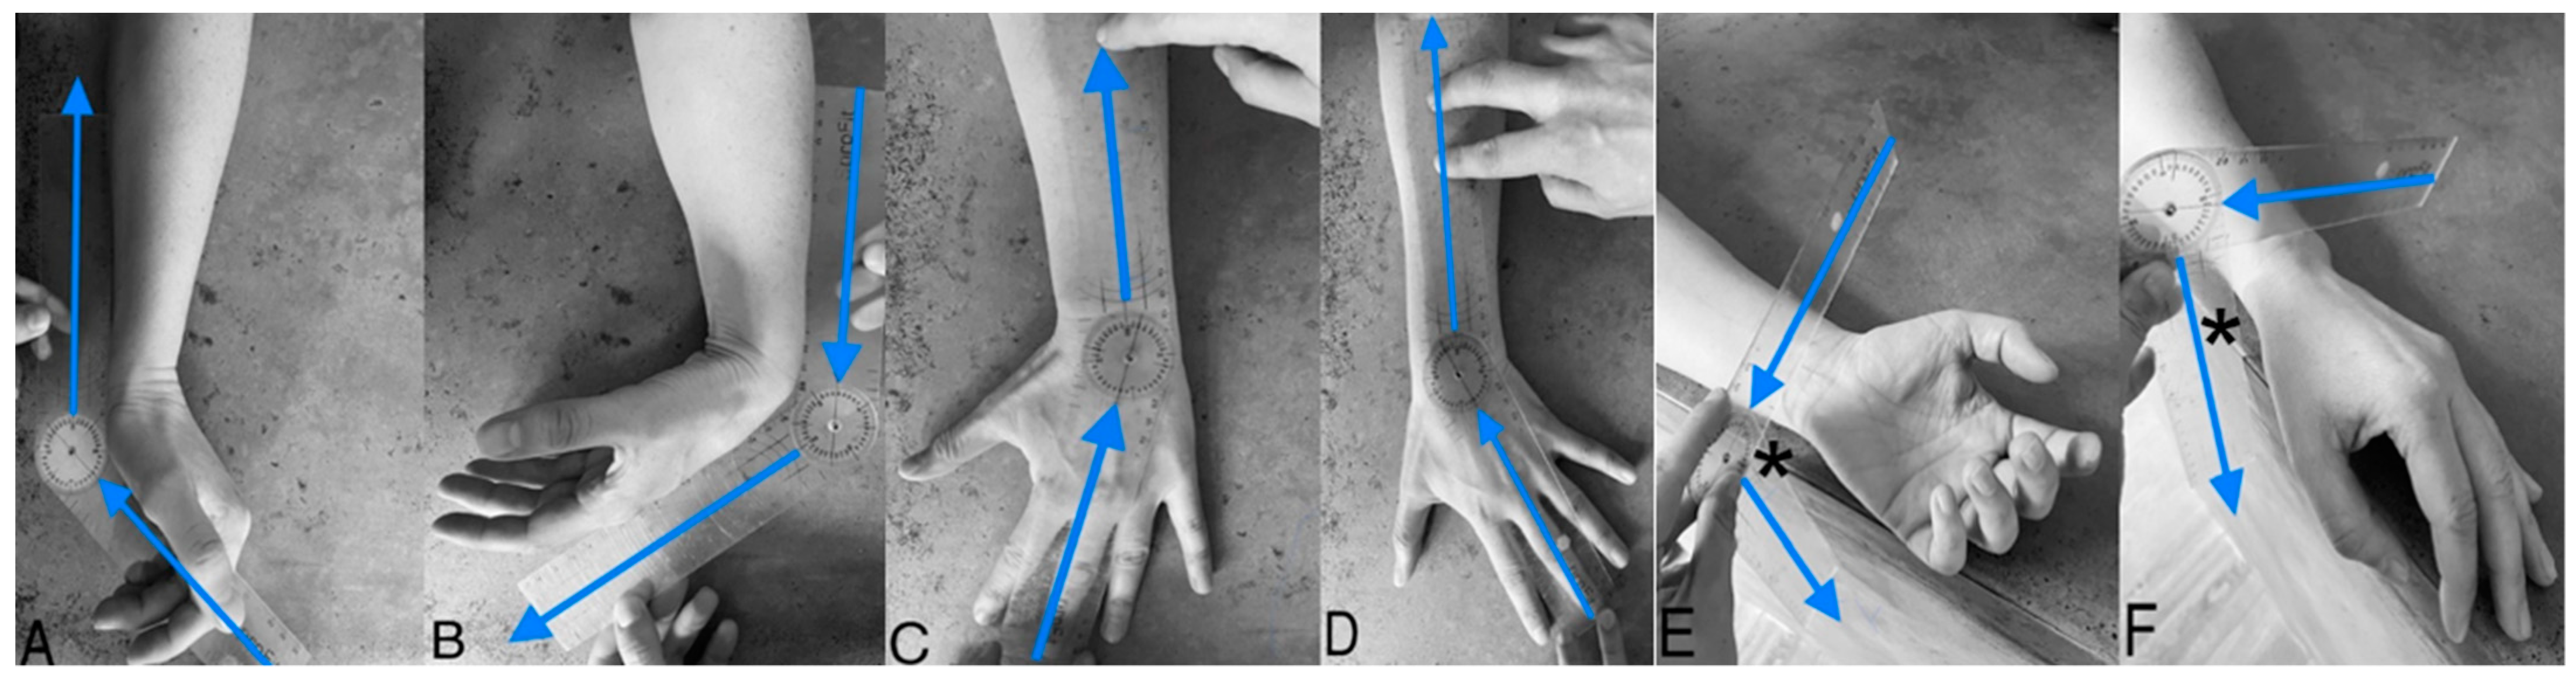

2.3. Goniometric Measurement